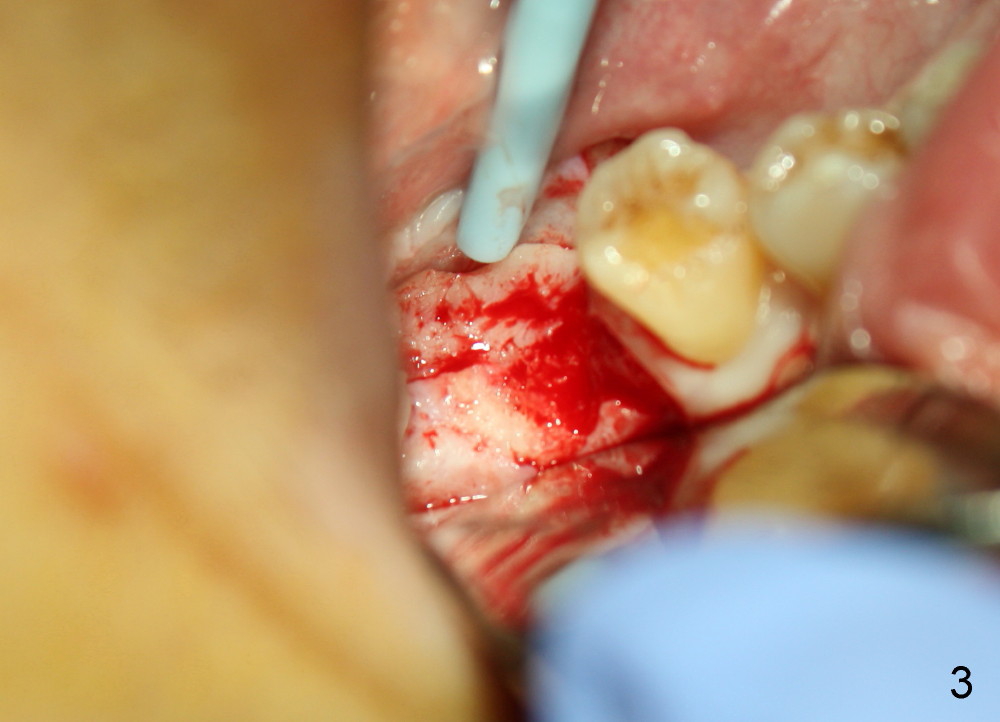

An incision is made instead of flapless, the socket is found to be filled with regenerated bone (Fig.3). After using 2 mm pilot drill, a paralleling pin is inserted to confirm trajectory and distance from the inferior alveolar nerve (Fig.4). Osteotomy is enlarged by Bicon reamers; threads are formed by insertion of Tatum 5x14 mm tap at the depth of 11 mm (Fig.5). The threads are visible when the tap is removed (Fig.6 ^). The advantage of using tap(s) is to test binding to the bone. If the tap is loose, the next sized tap should be used before placing a proper sized implant. This step is particularly critical when placing a large immediate implant or when the socket is immature.